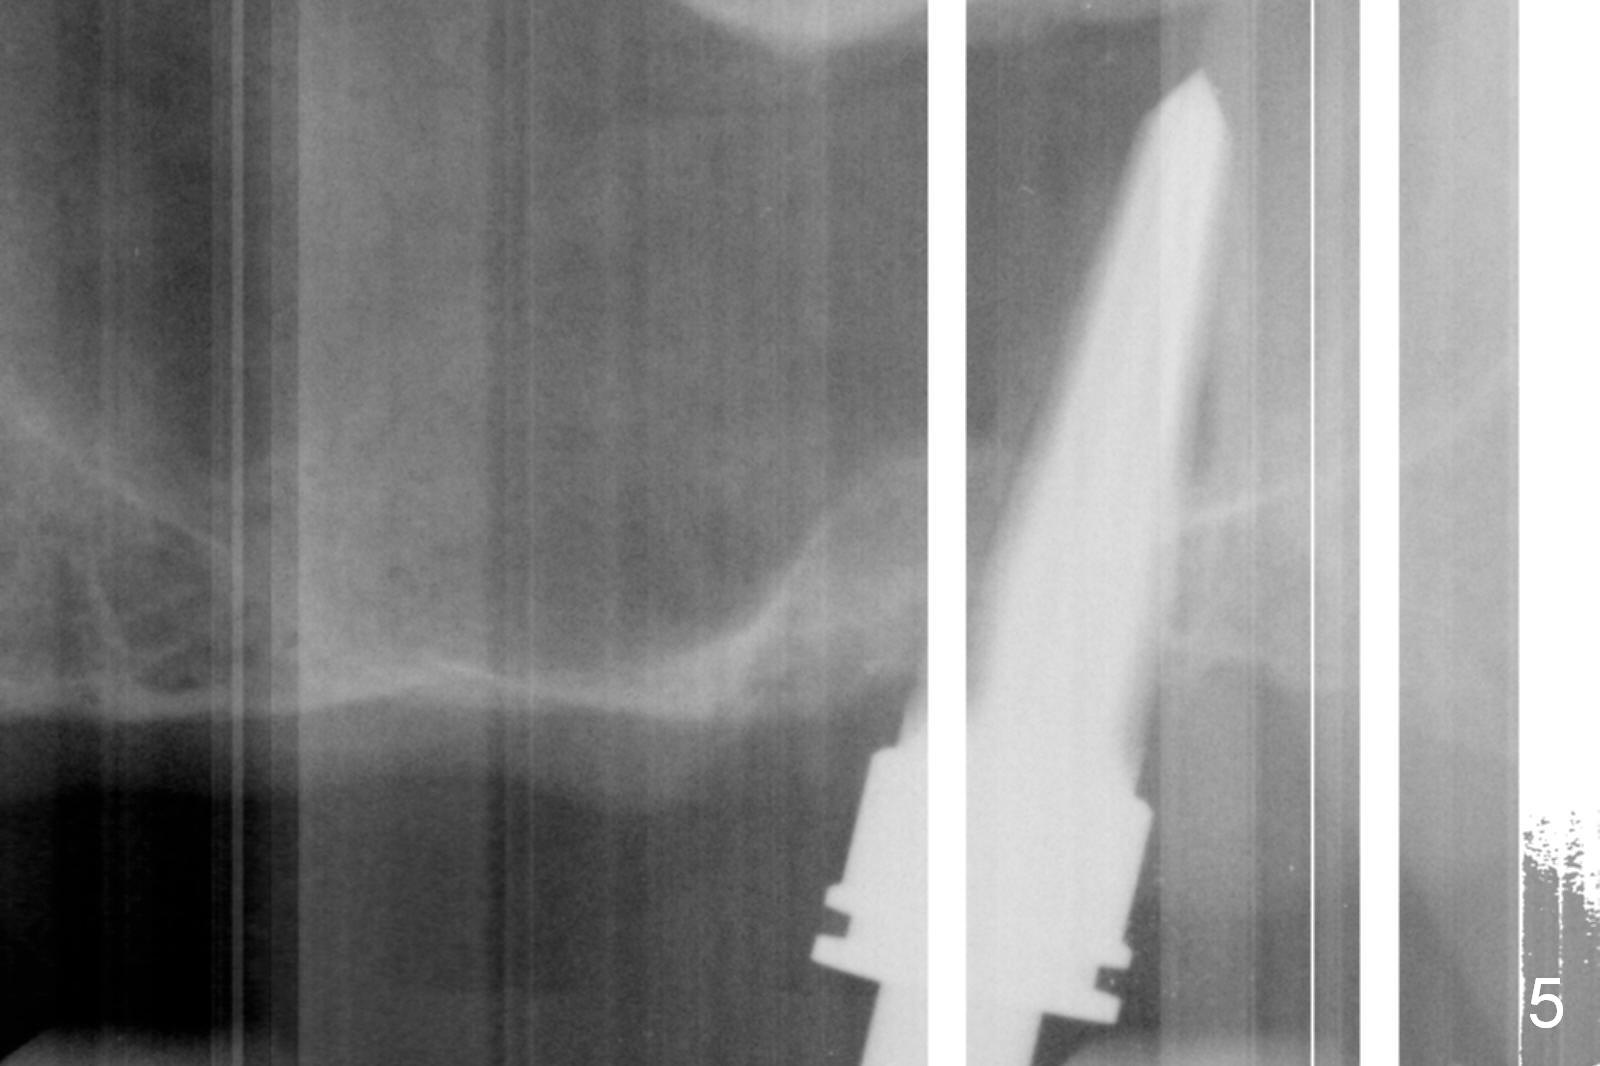

Fig.1,2 show the close relationship of the upper flipper and the residual roots at #15.  Atraumatic extraction using periotomes and surgical sectioning still results in perforation of the mesiobuccal socket (Fig.3 >).  The distobuccal one is shallow, while the septum is small.  It appears that the palatal (Fig.3 P) socket is the most ideal recipient site for the immediate implant and is expanded with Magic Osteotomes until 4.3 mm (Fig.4,5) with the coronal end pushed as buccal as possible.  After placing allograft for sinus lift (Fig.6 >), a 5x11 mm IBS implant is placed with insertion torque ~ 50 Ncm.  A 6x4(3) mm pair abutment is placed, followed by bone graft in the remaining sockets (Fig.6 *) and by Osteogen plug (Fig.7 *).  Finally the socket is sealed by applying acrylic over the abutment (Fig.8).  While the acrylic is setting, the flipper is seated and excess acrylic is removed and pushed away from the flipper (Fig.9).  Advise the patient not to wear the flipper.  If it is being worn, there will be minimal contact between the flipper and the immediate provisional.